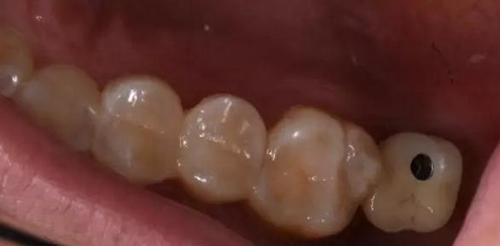

術(shù)后口內(nèi)照片

修復(fù)體戴入口內(nèi)后照片,與鄰牙鄰接良好。